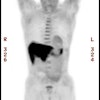

PET has been used to differentiate radiation injury from malignancy on the basis

of differences in glucose uptake. Recent studies have reported the sensitivity

and specificity of PET to be 81% to 86% and 40% to 94%, respectively. This